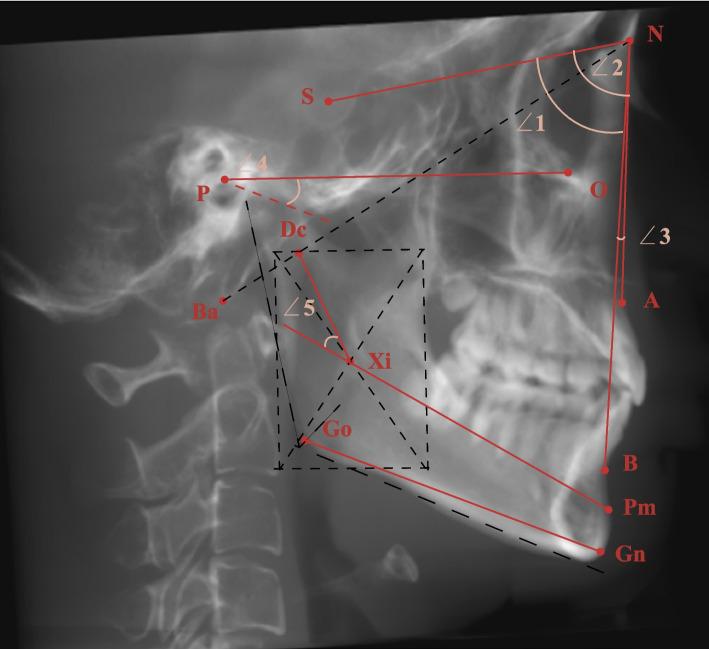

A total of 117 skeletal class II patients were divided into three groups according to the FH-GoGn angle (hypodivergent, normodivergent and hyperdivergent), with 40 class I normodivergent patients serving as controls. Each group contained two age subgroups (adolescents: 11-14 years old, adults: 18-35 years old). The size (condylar length, height, long and short axis diameter, glenoid fossa width and depth) and shape (condylar neck inclination, condylar head angle and long axis angle, articular eminence inclination) of the condyle and fossa, joint space (anterior, superior, posterior, mesial and lateral), and position of the fossa (vertical, transverse, and anteroposterior distance) and condyle were measured and compared using CBCT.

共纳入 117 例骨性 II 类患者,根据 FH-GoGn 角(低角、均角和高角)分为三组,其中 40 例 I 类均角患者作为对照组。每组分为青少年组(11-14 岁)和成年组(18-35 岁)。使用 CBCT 测量并比较髁突的大小(髁突长度、高度、长轴和短轴直径、关节窝宽度和深度)和形态(髁突颈倾斜度、髁突头部角度和长轴角度、关节结节倾斜度)、关节间隙(前、上、后、内、外侧)和关节窝位置(垂直、横向和前后距离)及髁突位置。